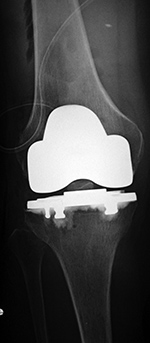

Stryker Triathlon PSC total knee arthroplasty

- posterior cruciate removal prosthesis |

There is also a surgical drain and skin staples in place. 65 year-old woman. |